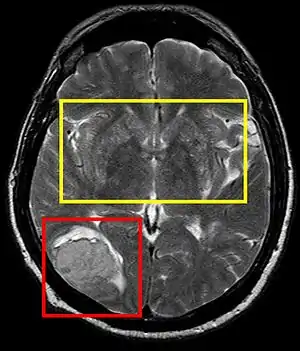

Cerebral softening, also known as encephalomalacia, is a localized softening of the substance of the brain, due to bleeding or inflammation. Three varieties, distinguished by their color and representing different stages of the disease progress, are known respectively as red, yellow, and white softening.[1][2]

| Stroke brain (similar to cerebral softening) | |